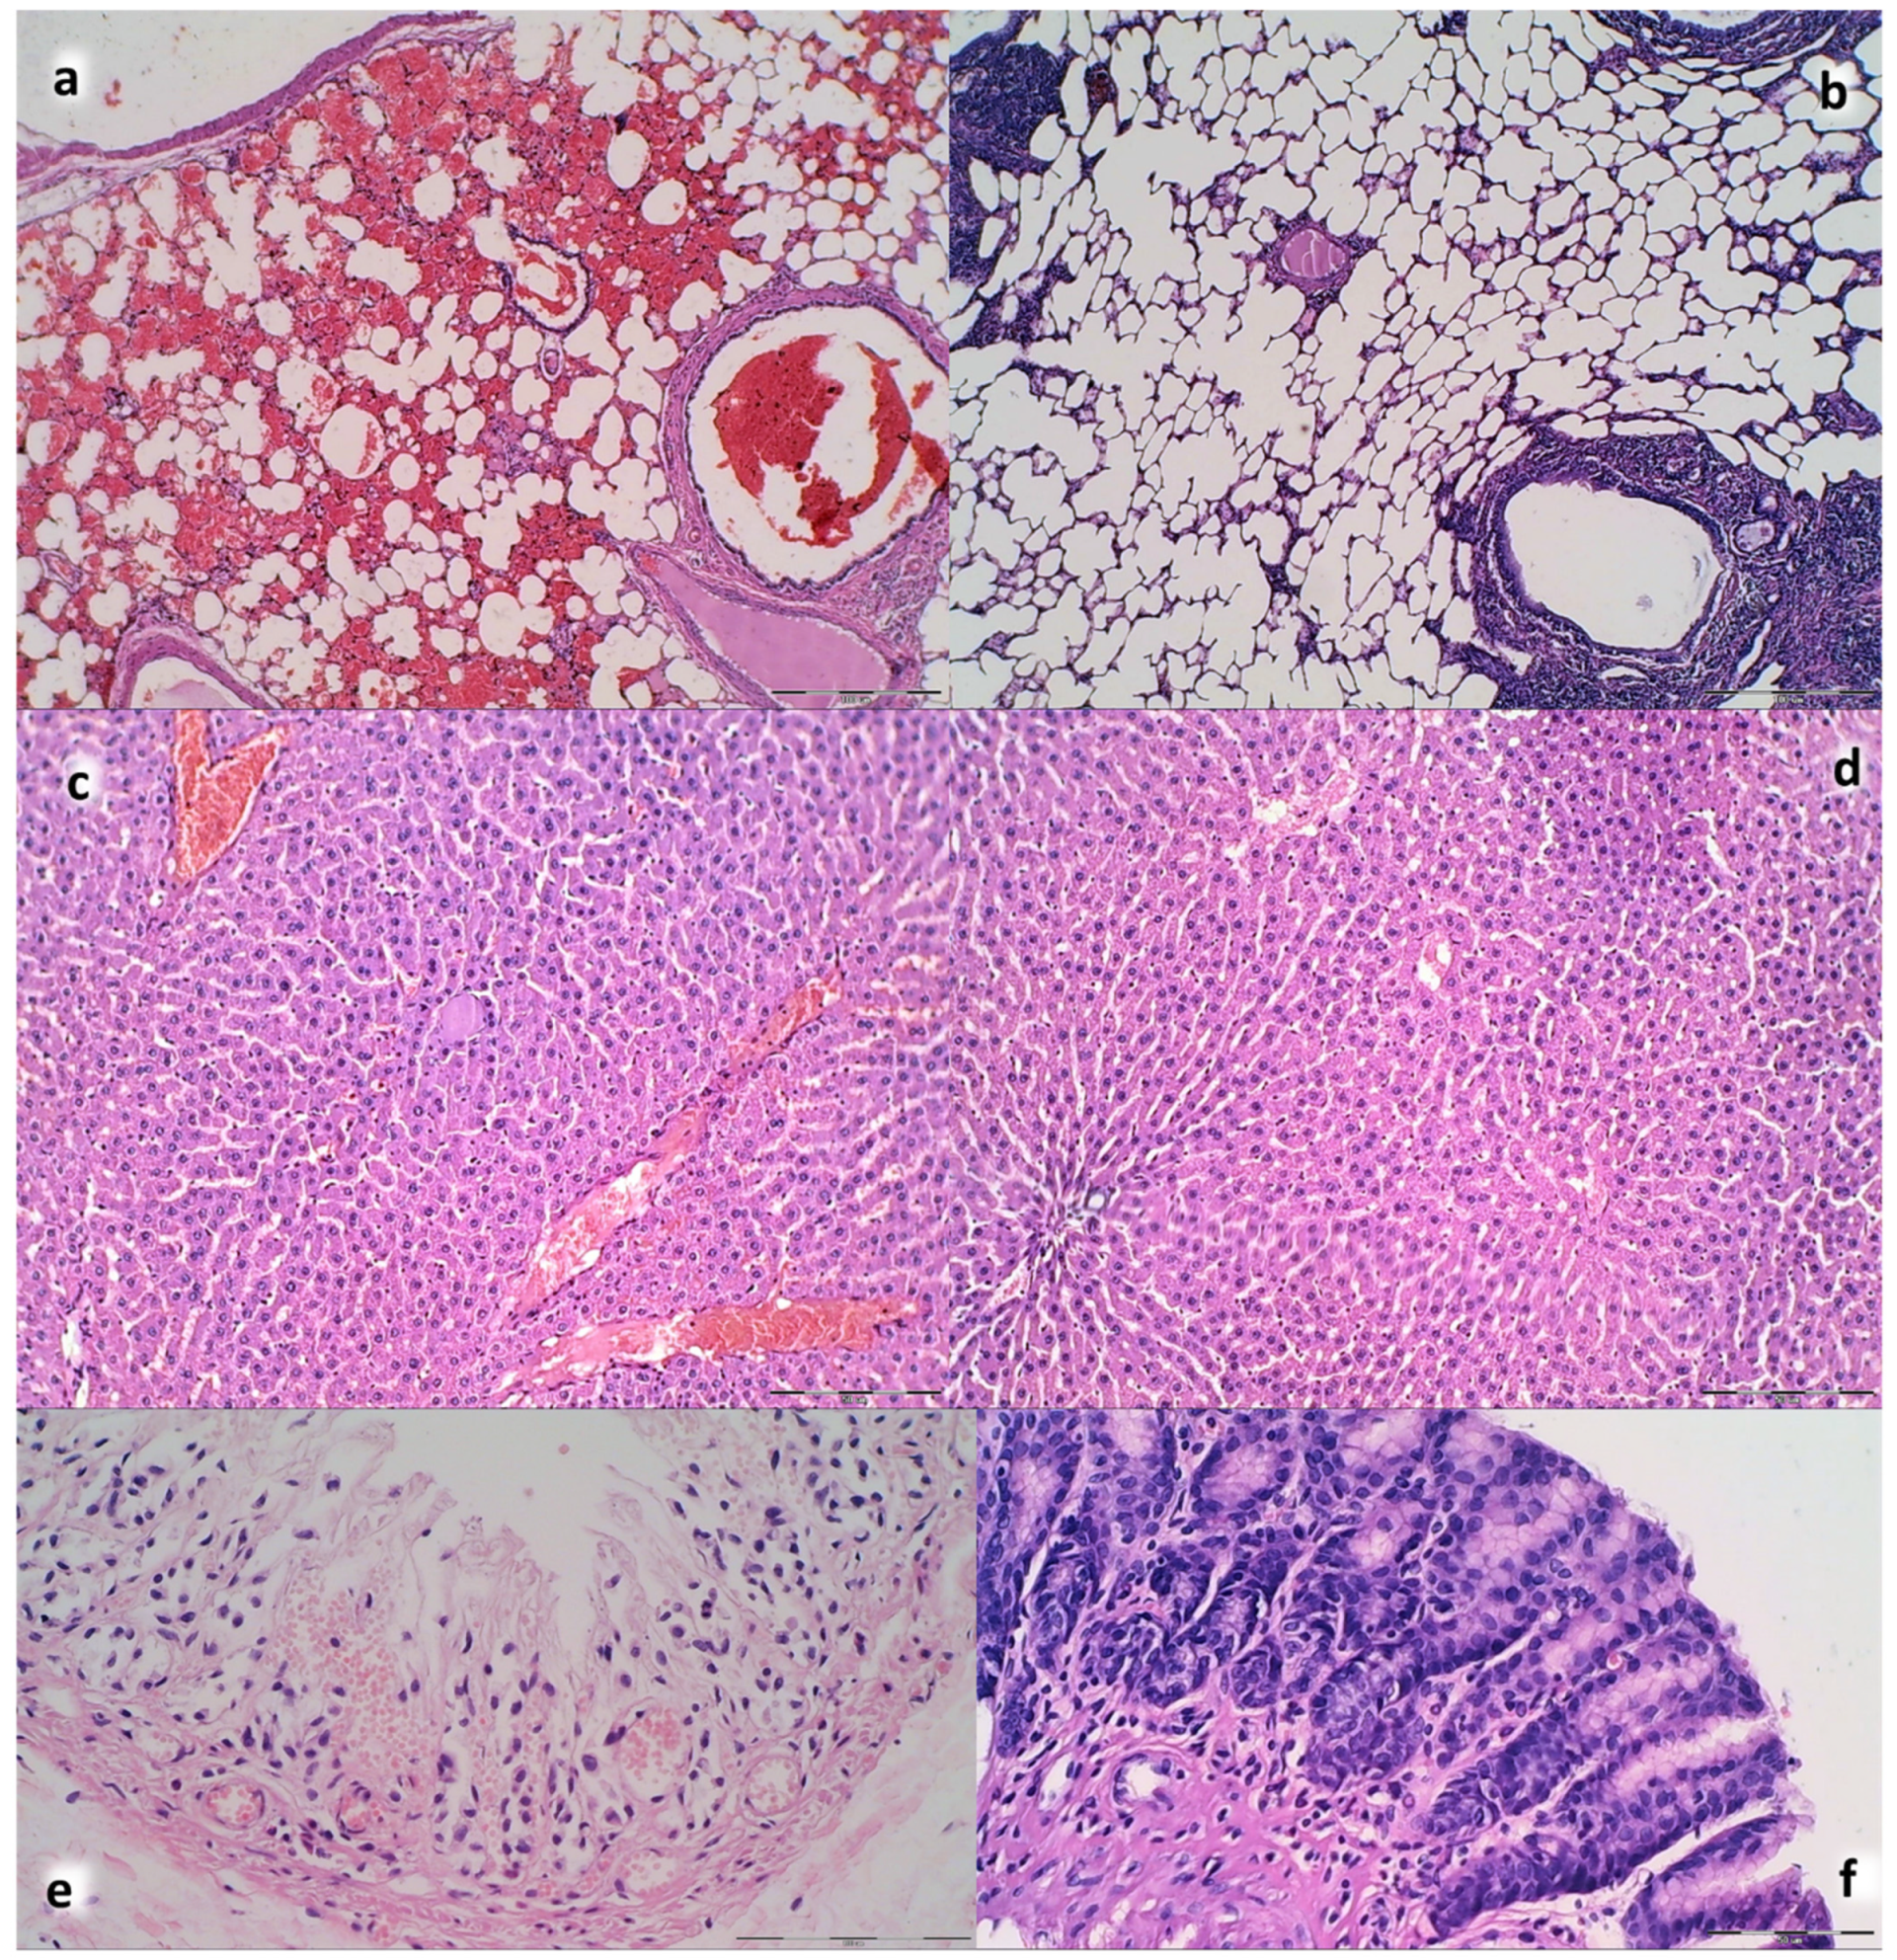

3.6. Stomach, Duodenum, Liver, Spleen, Ascites Presentation

3.9. Histology